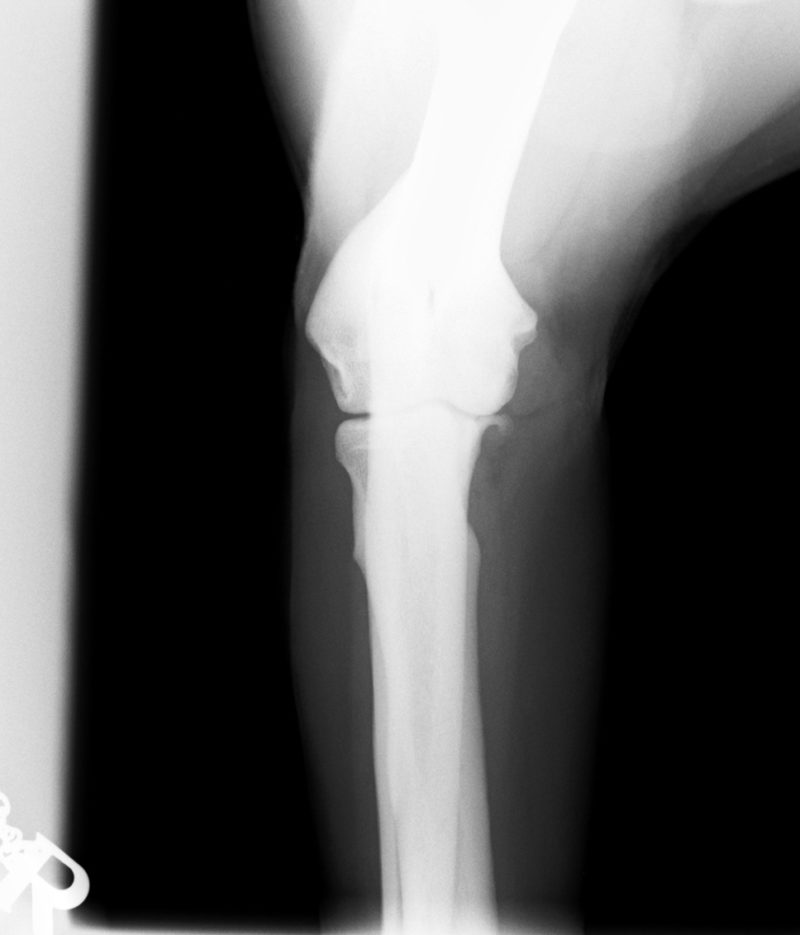

Ellenbogengelenksarthrose bei Labrador ...

Im August 2013 wurde ein acht Jahre alter männlich kastrierter Labrador mit beidseitig hochgradiger  Ellenbogengelenksarthrose vorgestellt. Der Hund war beidseits wegen eines frakturierten Processus Coronoideus (Der Proccesus Coronoideus stellt einen wichtigen knöchernen Stabilisator des Ellenbogengelenks dar) operiert, einseitig nachoperiert und auf beiden Seiten mehrfach mit Cortison-Injektionen behandelt worden.